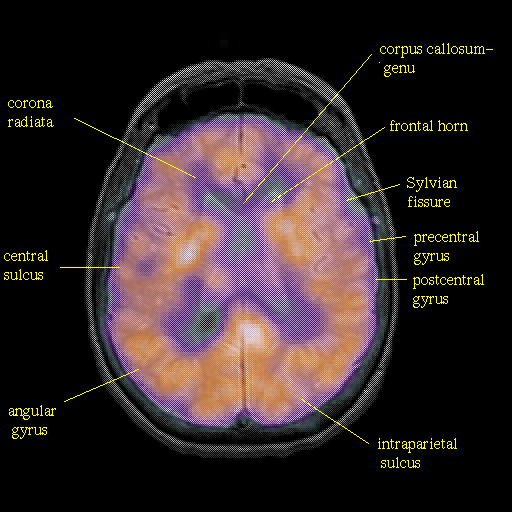

overlay : Slice 32

Slice 32

Pointers

Labeled

[Whole Brain Atlas Home Page] [Brain structure list] [Navigator Help Page]

Keith A. Johnson (keith@bwh.harvard.edu), J. Alex Becker (jabecker@mit.edu)